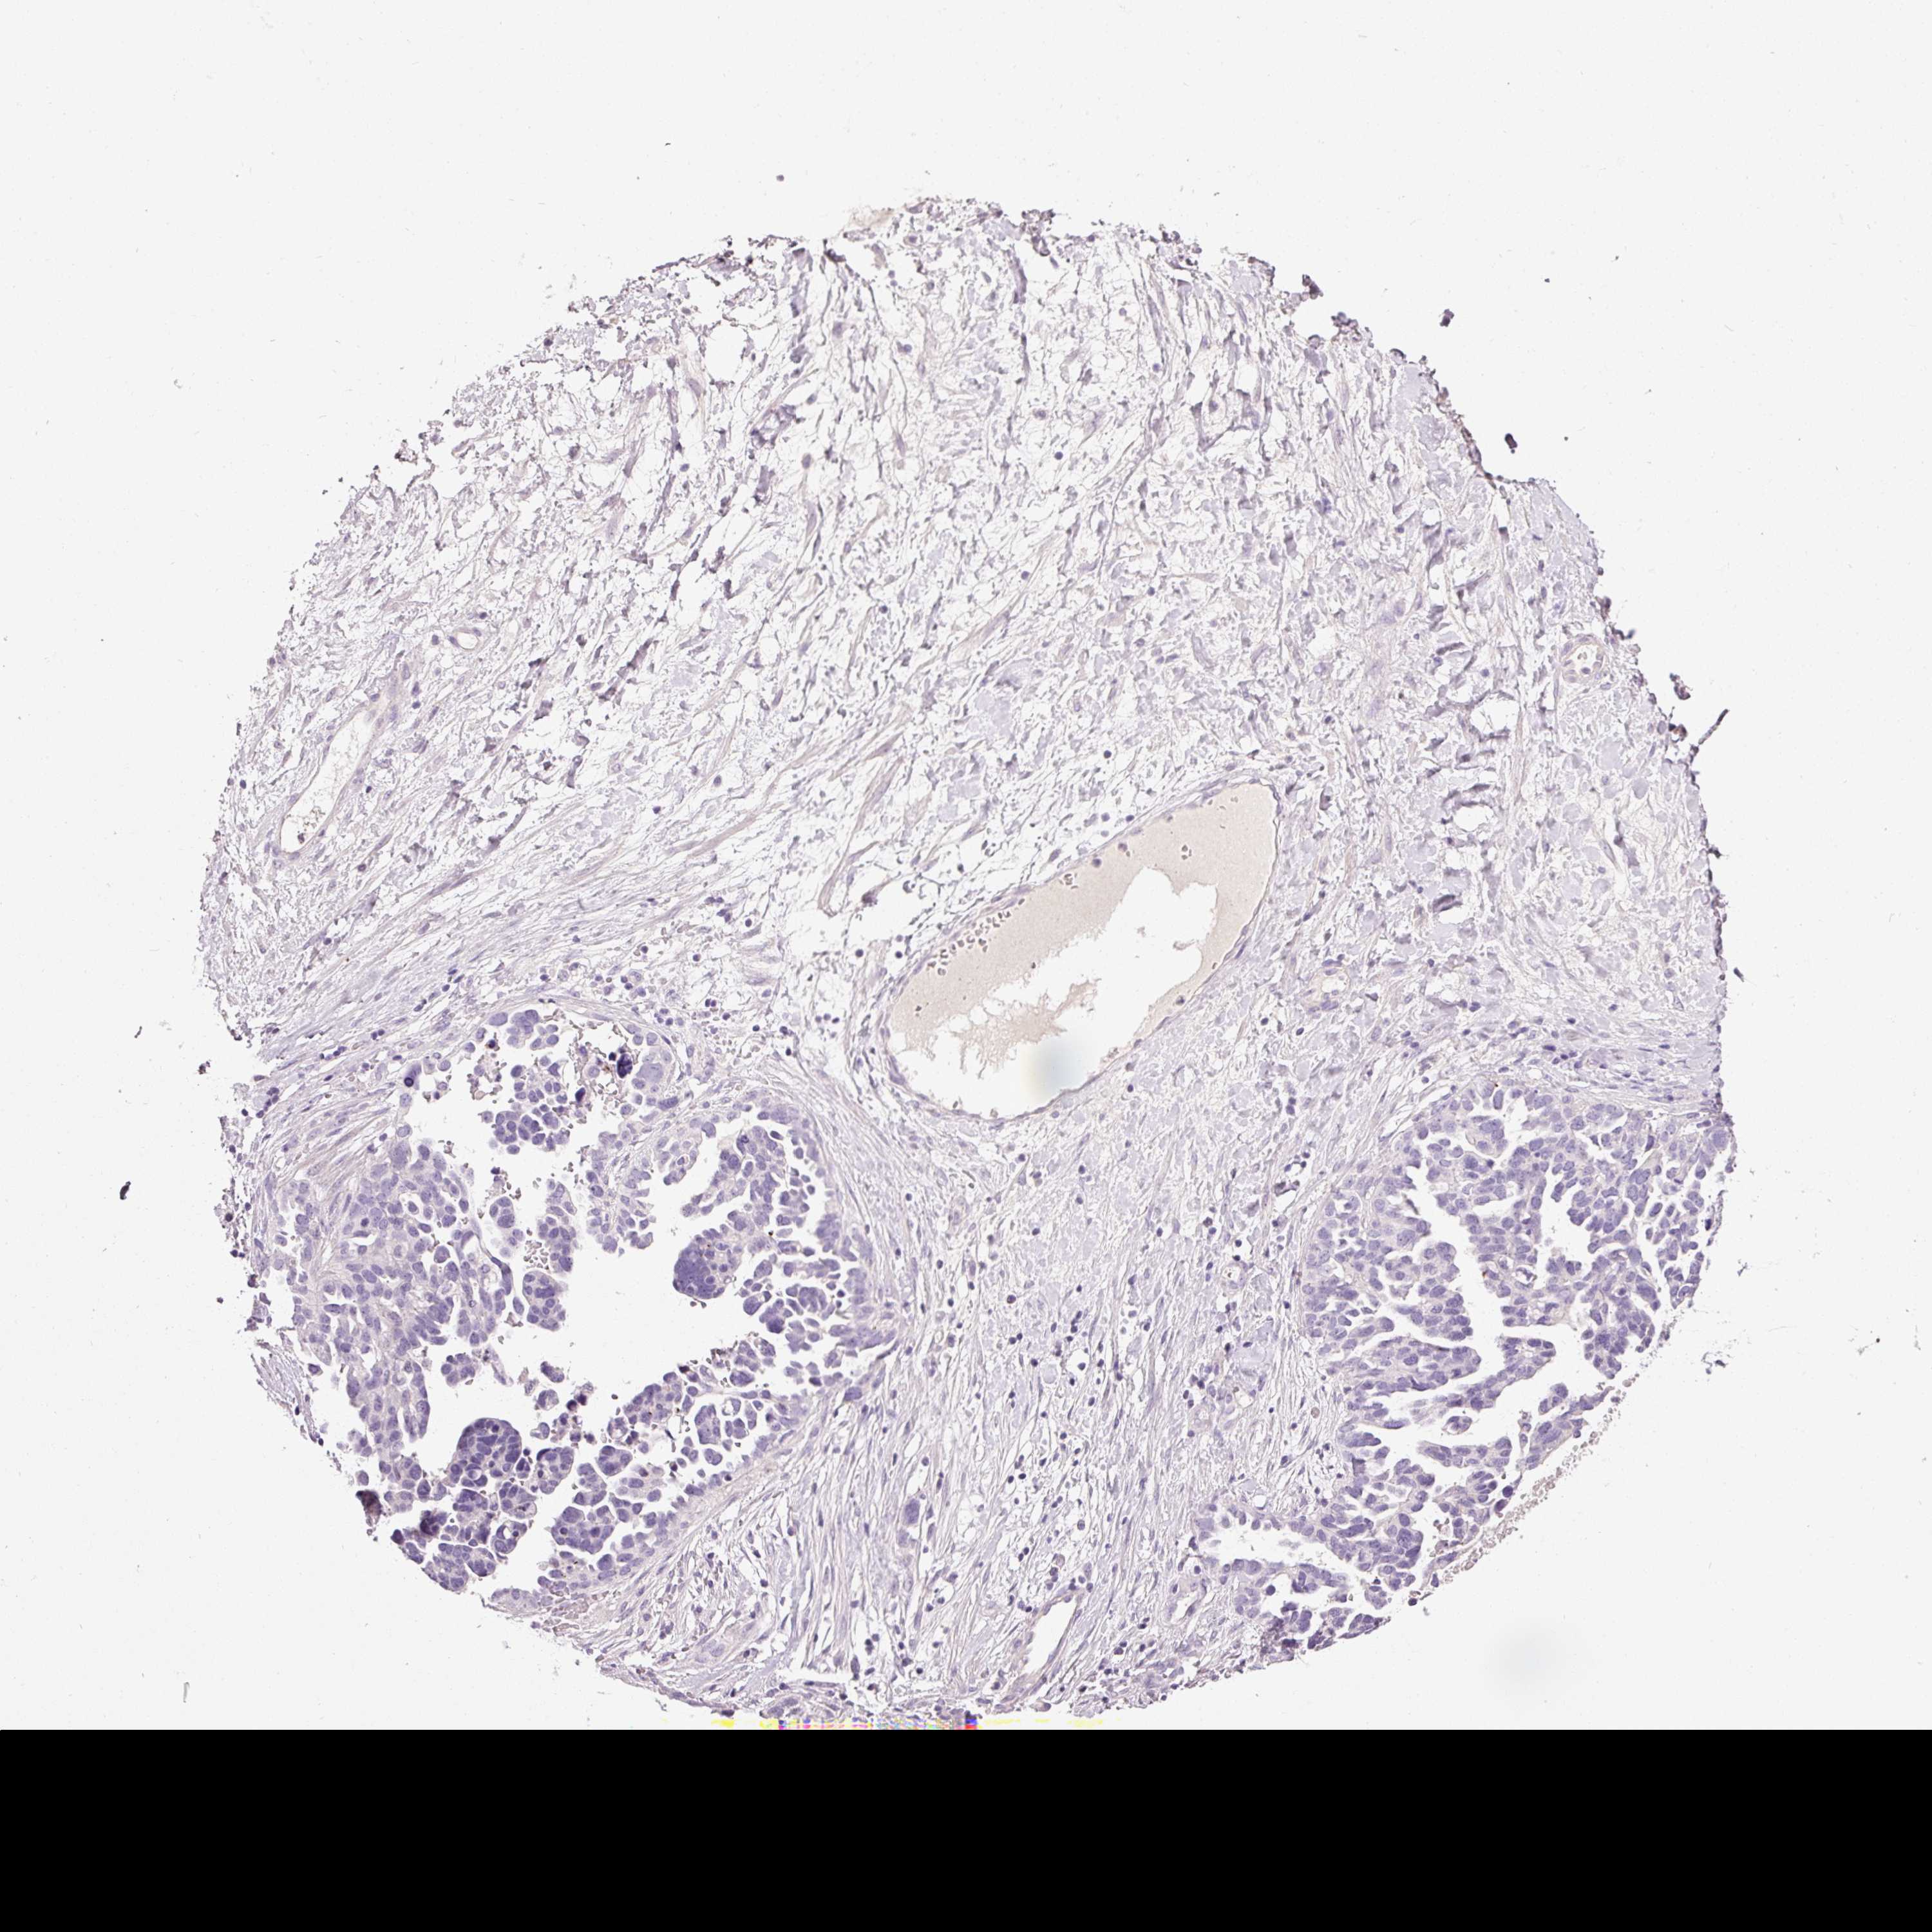

OVARIAN CANCER - Protein expressioni

A mouse-over function shows sample information and annotation data. Click on an image to view it in a full screen mode. Samples can be filtered based on level of antibody staining by selecting one or several of the following categories: high, medium, low and not detected. The assay and annotation is described here.

Note that samples used for immunohistochemistry by the Human Protein Atlas do not correspond to samples in the TCGA dataset.

Antibody stainingi

Antibody staining in the annotated cell types in the current human tissue is reported as not detected, low, medium, or high, based on conventional immunohistochemistry profiling in selected tissues. This score is based on the combination of the staining intensity and fraction of stained cells.

Each image is clickable and will lead to virtual microscopy that enables deeper exploration of all samples and also displays staining intensity scores, fraction scores and subcellular localization as well as patient and tissue information for each sample.

HPA040615

Cystadenocarcinoma, serous, NOS

Carcinoma, endometroid

Cystadenocarcinoma, mucinous, NOS

Carcinoma, NOS